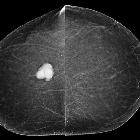

carcinosarcoma

Carcinosarcomas are highly malignant biphasic tumors with both carcinomatous (epithelial) and sarcomatous (bone, cartilage, or skeletal muscle) components.